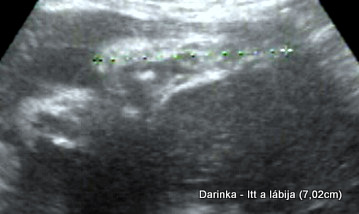

Darinka lába (7,02 cm)

Darinka lába (7,02 cm)